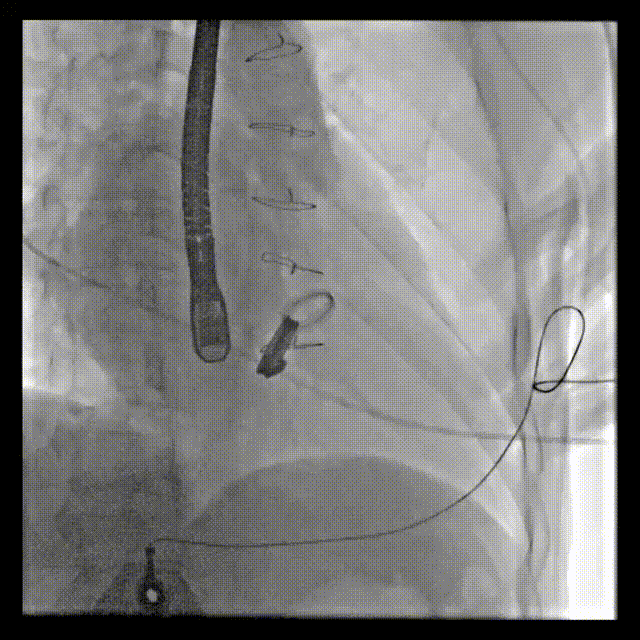

1.患者平卧位,食道超声检查瓣周漏位置及大小,并引导穿刺心尖,选择7F鞘管通过10点位置瓣周漏口,将单弯导管送入左心室,置换超硬导丝至左心室,选择12-14mmPDAO封堵10点位漏口。

3.选择7F鞘管通过1-2点位置瓣周漏,彩超显示鞘管对瓣周漏口的影响较小,结合漏口大小,选择14-16mmPDAO封堵此处漏口。

术后封堵器形态位置

手术全程顺利,术中出血100ml,使用造影剂40ml,共计用时1小时50分钟,术后患者无不适,安全返回普通病房,并于3天后出院。